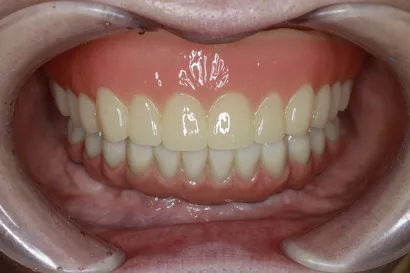

歯の欠損や見た目の不安は、笑顔や会話に大きな影響を与えます。「口を開けるのが恥ずかしい」「話すときに手で口元を隠してしまう」といったお悩みも少なくありません。全顎インプラント治療では、天然歯に近い色合いや形態の人工歯を用いることで、自然な口元を再現できます。見た目の改善はもちろん、食事の楽しさや会話のしやすさを取り戻すことにもつながります。

After執刀医 Dr.大杉 治療内容 虫歯・歯周病が原因で噛み合わせが崩壊していたので、全顎的なインプラント治療を行い、口腔機能の回復を行いました。

上顎:ピンクポーセレンを用いたフルジルコニアインプラントブリッジ

下顎:奥歯=ジルコニアインプラントブリッジ、前歯=ジルコニアクラウン治療期間 1年6ヶ月 費用 上顎:420万 税抜

After執刀医 Dr.大杉 治療内容 1回の手術でインプラントを埋め込み、即時の仮歯を装着して早期の機能回復を図りました。その後、噛み合わせを調整し、セラミックの製作を行いました。

上顎:ピンクポーセレンを用いたフルジルコニアインプラントブリッジ(All-on-4)

下顎:ピンクポーセレンを用いたフルジルコニアインプラントブリッジ(All-on-4)治療期間 1年 費用 上顎:330万 税抜

こうして得られるのは、しっかり噛める安心感と、自然で美しい歯並びや口元。日常の食事や会話に加え、笑顔の印象まで大きく改善できることを目指しています。